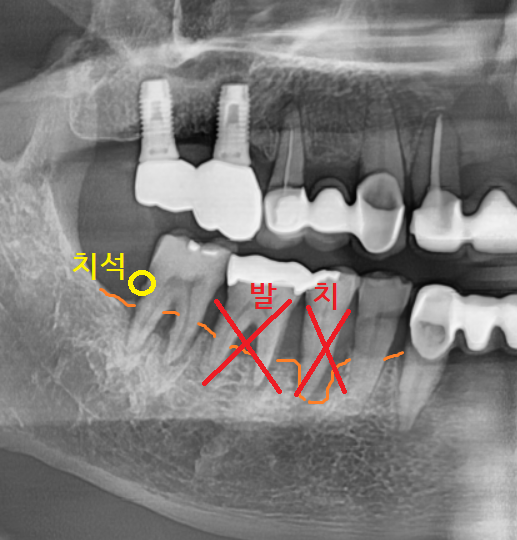

불편함을 호소하신 오른쪽 아래

잇몸뼈가 많이 내려가

치아 뿌리가 노출된 상황이었습니다.

검사를 해보았을 때

제일 많이 움직이는 치아

발치 후 임플란트 하기로 상담해 드렸습니다.